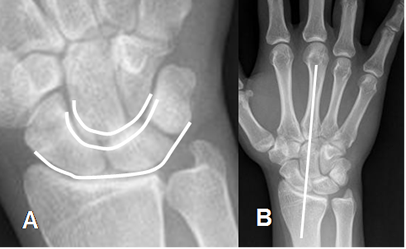

En una Rx AP, los huesos del carpo están alineados en 3 arcos I, II y III, los cuales son paralelos entre si. Igualmente hay coincidencia entre el eje del radio y el del 3º metacarpiano. Una interrupción en alguna de estas líneas indica fractura o luxación. (8). (Fig 10).

Fig 10. Alineación ósea.

A: Rx AP. Alineación de los 3 arcos del carpo.

B: Rx AP. Alineación entre el eje de radio y el 3º metacarpiano.